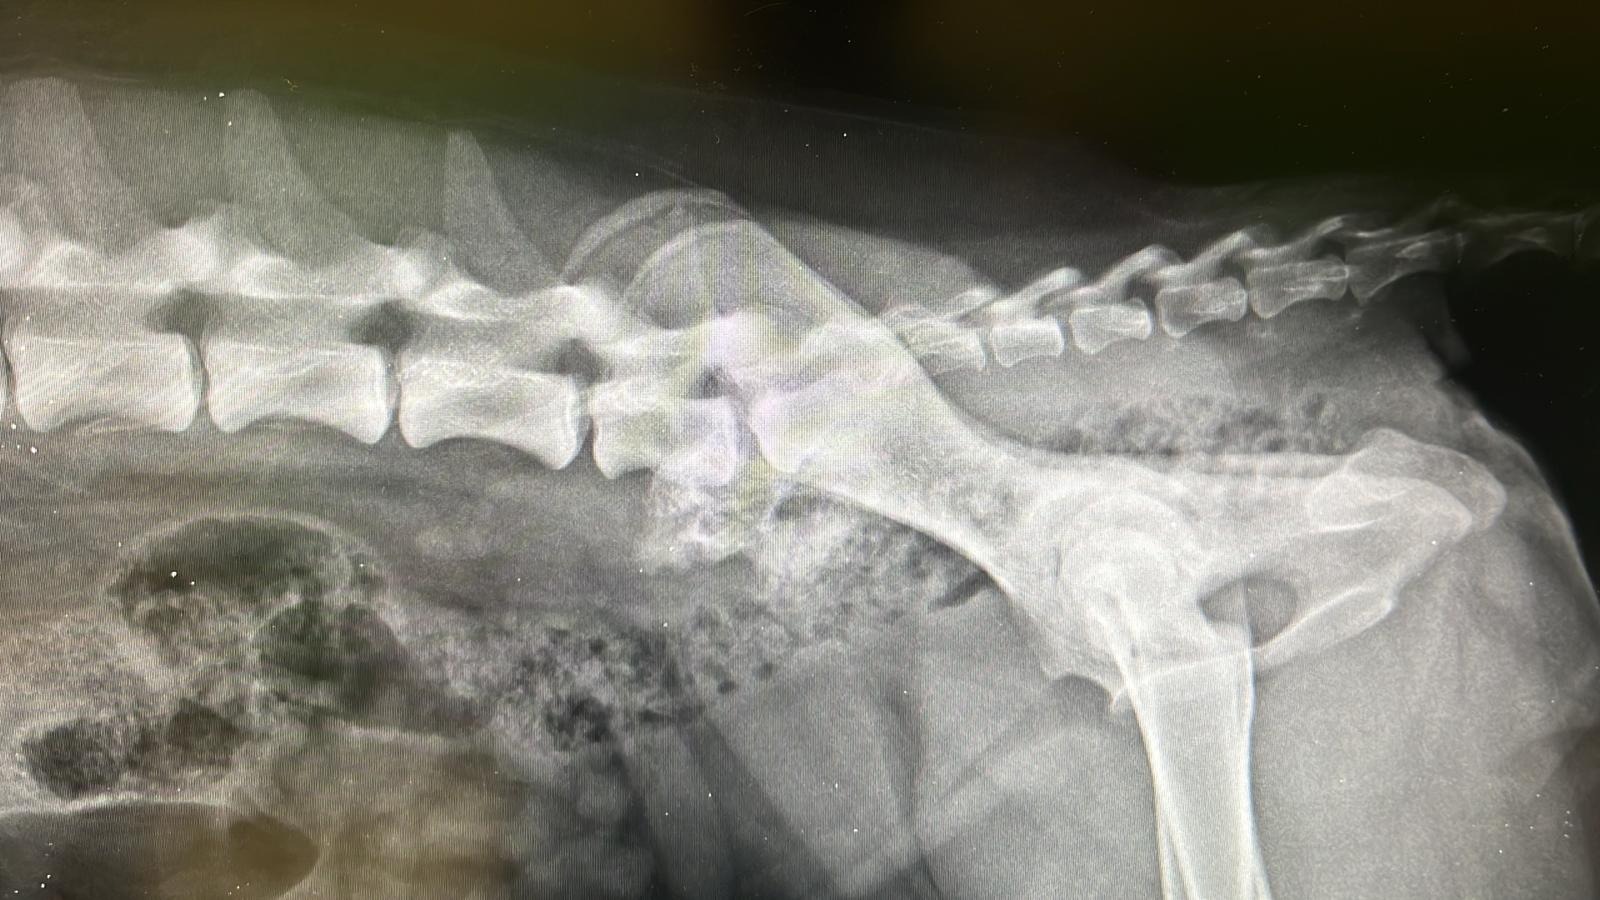

Purtroppo la mia situazione è un disastro: ho un brutto problema all'anca sinistra e alla regione sacroiliaca, non appoggio la zampa e non ho muscolo, la diastasi sacroiliaca non si sa se sia conseguente ad un investimento o a delle botte, ma sicuramente ha origine traumatica, sarà necessario effettuare una risonanza magnetica e una visita neurologica per capire se e come procedere per inserire una protesi nella mia anca che mi permetta di camminare e mi possa dare una vita "normale".